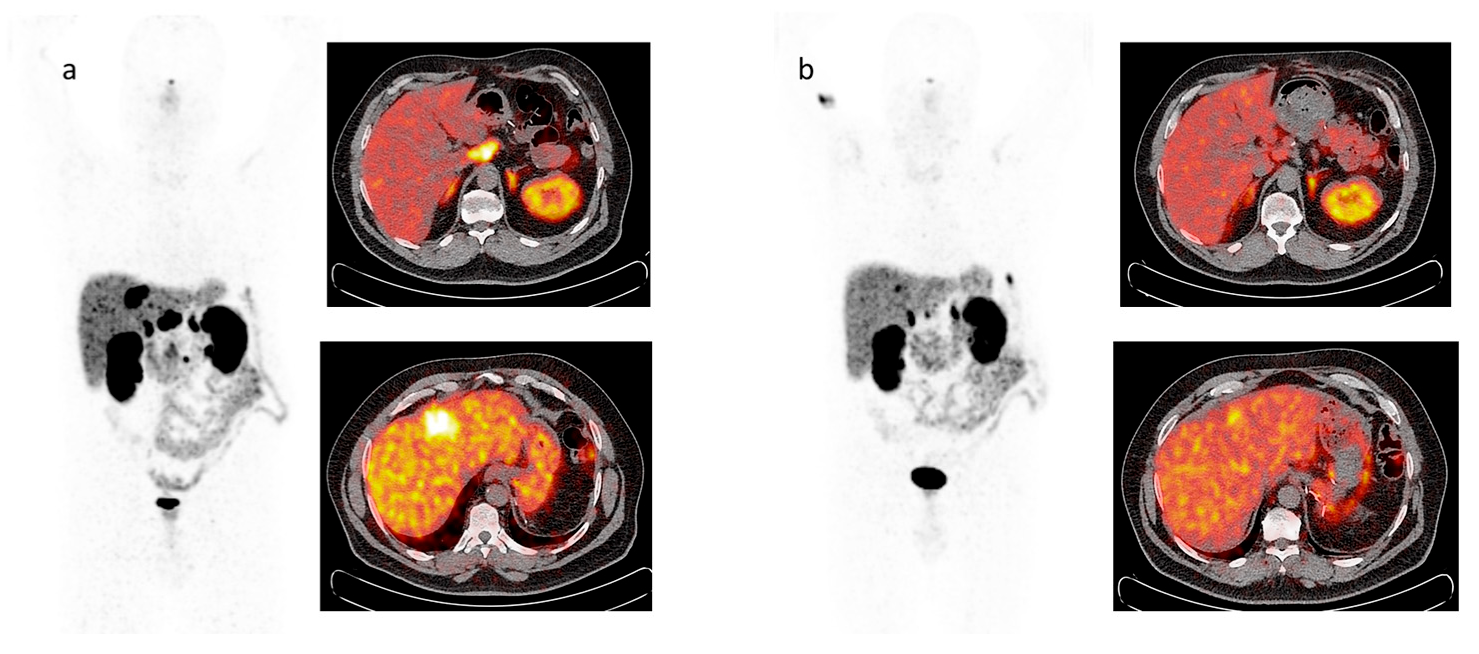

6. Functional Imaging by 18F-FDG PET/CT

7. PRRT by Radiolabeled Somatostatin Analogs

- Ambrosini, V.; Kunikowska, J.; Baudin, E.; Bodei, L.; Bouvier, C.; Capdevila, J.; Cremonesi, M.; de Herder, W.W.; Dromain, C.; Falconi, M.; et al. Consensus on molecular imaging and theranostics in neuroendocrine neoplasms. Eur. J. Cancer 2021, 146, 56–73. [Google Scholar] [CrossRef]

- Binderup, T.; Knigge, U.; Johnbeck, C.B.; Loft, A.; Berthelsen, A.K.; Oturai, P.; Mortensen, J.; Federspiel, B.; Langer, S.W.; Kjaer, A. 18F-FDG PET is Superior to WHO Grading as a Prognostic Tool in Neuroendocrine Neoplasms and Useful in Guiding PRRT: A Prospective 10-Year Follow-up Study. J. Nucl. Med. 2021, 62, 808–815. [Google Scholar] [CrossRef]

- Cingarlini, S.; Ortolani, S.; Salgarello, M.; Butturini, G.; Malpaga, A.; Malfatti, V.; D’Onofrio, M.; Davì, M.V.; Vallerio, P.; Ruzzenente, A.; et al. Role of Combined 68Ga-DOTATOC and 18F-FDG Positron Emission Tomography/Computed Tomography in the Diagnostic Workup of Pancreas Neuroendocrine Tumors: Implications for Managing Surgical Decisions. Pancreas 2017, 46, 42–47. [Google Scholar] [CrossRef]

- Sansovini, M.; Severi, S.; Ianniello, A.; Nicolini, S.; Fantini, L.; Mezzenga, E.; Ferroni, F.; Scarpi, E.; Monti, M.; Bongiovanni, A.; et al. Long-term follow-up and role of FDG PET in advanced pancreatic neuroendocrine patients treated with 177Lu-D OTATATE. Eur. J. Nucl. Med. Mol. Imaging 2017, 44, 490–499. [Google Scholar] [CrossRef]

- Severi, S.; Nanni, O.; Bodei, L.; Sansovini, M.; Ianniello, A.; Nicoletti, S.; Scarpi, E.; Matteucci, F.; Gilardi, L.; Paganelli, G. Role of 18FDG PET/CT in patients treated with 177Lu-DOTATATE for advanced differentiated neuroendocrine tumours. Eur. J. Nucl. Med. Mol. Imaging 2013, 40, 881–888. [Google Scholar] [CrossRef]